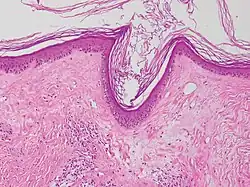

| Lichen sclerosus | Hyperkeratosis, atrophic epidermis, sclerosis of dermis and dermal lymphocytes.[7] |

| ||